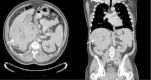

Case presentation: A 60 year old male with no relevant past medical history was referred to the endocrinology clinic with 18 month history of episodic hypoglycemic symptoms and, on one occasion was noted to have a fingerstick glucose of 36 mg/dL while having symptoms of hypoglycemia. Basic laboratory evaluation was unrevealing. Further evaluation however showed an elevated serum IGF-2 level at 2215 ng/mL (reference range 411-1248 ng/mL). Imaging demonstrated a large right suprarenal mass. A right nephrectomy with resection of the mass demonstrated a malignant solitary fibrous tumor. Post resection, the patient's IGF-2 levels normalized and hypoglycemic symptoms resolved.